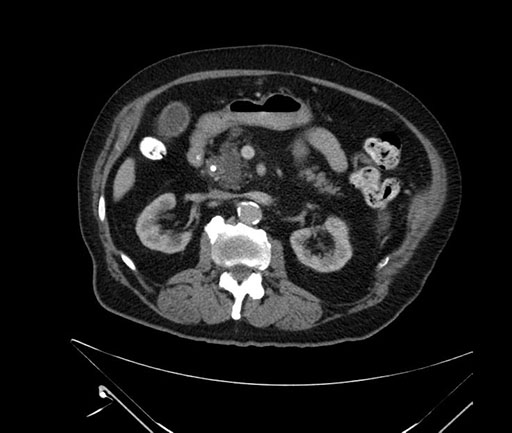

Imaging Analysis

Look through the patient's CT scan to identify any areas of concern for the necessary procedure.

Based on your CT findings, which issue(s) would give reason for "planned slowing down moment(s)" in this case?

Considering a standard Whipple procedure, what step(s) of the operation would you do differently in this case?